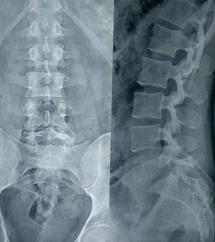

A 30-year-old manual laborer working in Middle East, presented to us with severe pain in the lower back (VAS-8) with the right lower limb radiculopathy for 6 months. Radiological investigations revealed to have a solitary osteolytic lesion with pathological fracture at L5 vertebral body. MRI showed hyperintense lesion in T2 sagittal images and hypointense in T1 sagittal images in L5 vertebral body. PET scan showed metabolically active lesion involving L5 vertebra body and right ischium. CT-guided biopsy from L5 vertebral body was performed, but was inconclusive. The patient underwent surgical management in the form of posterior stabilization L4-S1 and transpedicular biopsy. The sample was sent for frozen section and confirmed the presence of neoplasia but did not provide sufficient information about the nature of pathology. Intraoperatively, the decision was made to do anterior excision biopsy, corpectomy, and reconstruction with titanium mesh cage filled with cement. The precise diagnosis of LCH was established on histopathological examination and confirmed with immunohistochemistry positivity for CD1a and S100. The patient had immediate relief of his back pain and radicular pain. He was able to resume his daily activities at 1 month after the surgery. At 2-year follow-up patient was asymptomatic and no local recurrence was noticed.

Surgical excisionfor LCH in adults should be considered in patients with refractory low back pain with pathological fracture, neurological deficits, or spinal instability.